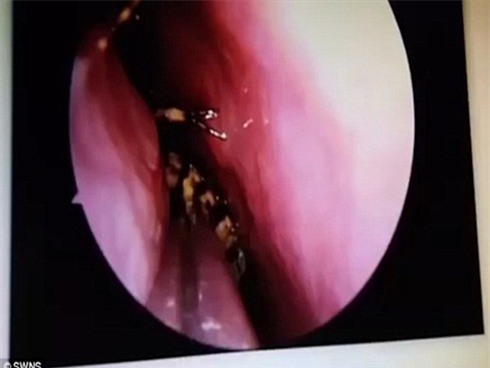

Để gắp được con gián ra khỏi hộp sọ của người phụ nữ, các bác sĩ đã phải sử dụng tới máy hút và nhíp trong ca phẫu thuật kéo dài 45 phút đồng hồ.

Con gián đã chui được vào gần não của người phụ nữ.